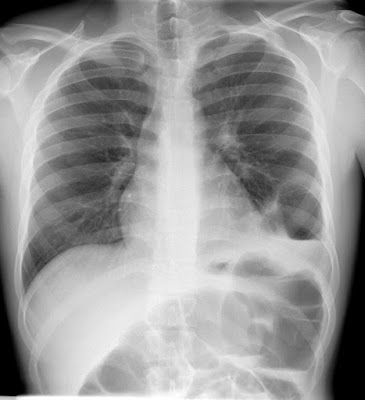

Μία άλλη μέθοδος με την οποία μπορεί να αναδειχθεί η παρουσίαδιαφραγματοκήλης είναι η ακτινολογική απεικόνιση. Η απλή ακτινογραφία θώρακα σε σπάνιες περιπτώσεις μπορεί να είναι χρήσιμη, καθώς απεικονίζεται η γαστρική φυσαλίδα δηλαδή ο αέρας του εσωτερικού του στομάχου μέσα στο θώρακα. Η μέθοδος που χρησιμοποιείται συνήθως είναι η ακτινολογική απεικόνιση μετά την κατάποση βαρίου, ενός σκιαγραφικού υλικού. Με αυτόν τον τρόπο απεικονίζεται ακτινολογικά ο πεπτικός σωλήνας και αποκαλύπτεται ηδιαφραγματοκήλη. Σε κάθε ακτινολογικό έλεγχο με βαριούχο γεύμα ο ασθενής τοποθετείται σε θέση TRENDELEBURG 20 μοιρών (κεφάλη κάτω) έτσι ώστε να αναδειχτεί η γαστροοισοφαγική παλινδρόμηση.